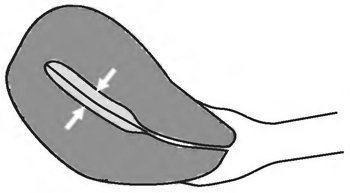

Vastagság M-echo

Reakcióvázlat meghatározó vastagsága M-echo méh

1. Mérjük a vastagsága a M-visszhang hosszanti méh szkennelés egyidejű megjelenítését a méhnyakon.

2. Az endometrium vastagságát feltételezik maximális anterioposterior mérete M-echo (endometrium két réteg).

3. Mérési hordoz mentén a külső kontúrok a M-echo méh merőleges a hosszirányú tengelyre.